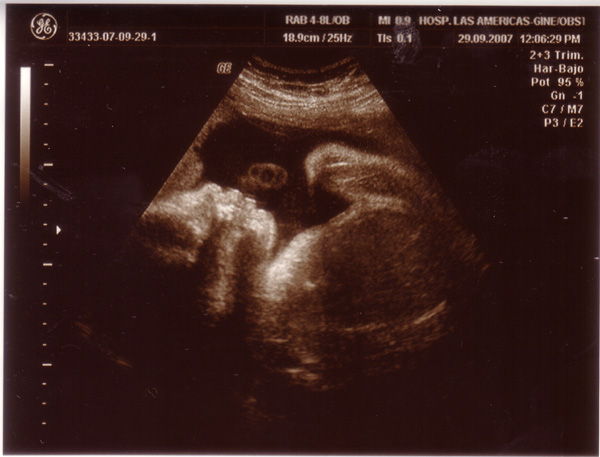

Szóval, aug 31-én voltam 30+1 idősen a III. rutinon és a 30. heti UH-on. Az UH-n már sejtettem, hogy valami nagy baj lesz, mert a nem mindeig kedves UH-s nő volt szolgálatban, és csak annyit mondott, hogy ő úgy látja, hogy kisebb a baba a koránál, de majd csak az orvos tudja megmondani, hogy mi van. Megpróbált dokit keríteni, de nem volt szabad egyik sem, ezért visszahívott du 1/2 1-re. 1/2 2-kor meg is jelent a doki, és az UH-s nő olyan kedvesen szólított be, mint még soha ( itt már tudtam, hogy nagy a baj...) Sokáig nézegetett, és azt mondta, hogy rossz hír, hogy a méhlepényem nem jól működik (szinte sehogy), és menjek fel a szülőszobára, majd ott megmondják a további teendőket. Felmentem, elkezdték rögzíteni az adataimat, mire megjelent a főorvos, és közölte, hogy mivel ők nem vállalnak 32 hetes kor előtt szülést, fel kell mennem Pestre. (Így tudtam meg, hogy meg kell szülnöm a babámat-ennyit az együttérzésről.) Rámrakták a ctg-t, de szerintem csak azért, mert várni kellett a mentőre. Kb fél óra múlva jött is a mentő, addig Ricsi hazaszaladt a kórházi pakkomért, és rögtön vittek is fel a SOTE I-re, mert a II nem fogadott. Amikor odaértünk, már nagyon vártak menket, rögtön csináltak még egy UH-t, aminek ugyanaz lett az eredménye, mint a Starjáninak, csak ott 1000 g-ra becsülték a súlyát, itt meg csak 710 g-ra. Elmondták, hogy a méhlepényem el van öregedve, szinte alig működik, és a baba már csak visszafelé fejlődött az utóbbi napokban, rögtön császározni kell. Előkészítettek a császárhoz, és mondanom kellett két nevet (egy fiút és egy lányt). Talán ez volt a legnehezebb, mert mi még egyáltalán nem voltunk felkészülve sem a szülésre, sem a névválasztásra, igaz hogy volt egy-két befutónk, de még nem volt eldöntve, mert még azt sem tudtuk, hogy kisfiunk lesz-e vagy kislányunk. Felhívtam Ricsit, és eldöntöttük, hogy akkor legyen Fruzsina és Kristóf. Már toltak is be a műtőbe, beadták az érzéstelenítőt, és este 19 óra 40 perckor már meg is született Kristóf 910 grammal és 34 cm-rel. Nekem csak egy pillanatra mutatták meg, de addigra már megérkeztek Ricsiék is, és ő megnézhette a koraszülött intenzív osztályon. Szegénykém olyan kis lila volt, meg véznácska, de most már kész kislegény!